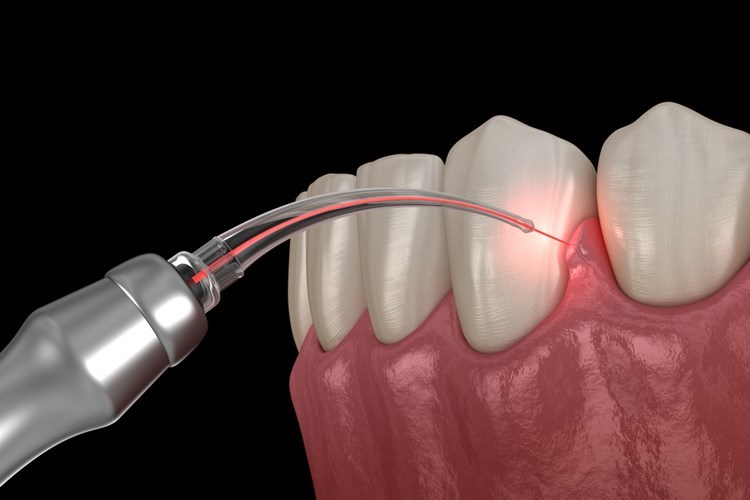

מהי הקצעת שורשים ומהם שלבי הטיפול במחלות חניכיים?

"הקצעת שורשים" הוא טיפול שמבצע מומחה החניכיים כדי לסלק את משקעי החיידקים גם מהכיסים העמוקים ביותר. הטיפול הזה משלים ניקוי אצל שיננית ומבוצע רק אחת לשנתיים.

בשלב הראשון, רופא החניכיים אוסף נתונים על הפה שלכם כדי לאבחן אם אתם אכן סובלים ממחלת חניכיים, או שהתסמינים מעידים על מחלה אחרת. לאחר שאובחנה מחלת החניכיים, מתחיל החלק הראשון של הטיפול, שמטרתו לטפל בדלקת שנוצרה. בשלב זה מסירים את רובד החיידקים והמשקעים שהצטבר על פני השטח של השן ויצרו את הדלקת.